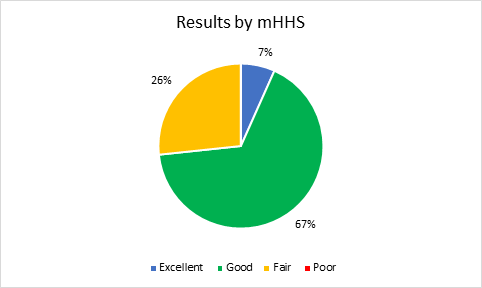

A total of twelve patients (15 hips), who met the required criteria were chosen for GM repair. All of them were women with an average age of 56.66 years (42-70). The mean follow-up period was 11 months (4-24). The demographic data is illustrated in Table 1. The median mHHS improved from 68 points (interquartile range [IQR], 59, 68 points) preoperatively to 82 points (IQR, 76, 88 points) at the latest follow-up (p=0.001) Table 2, Graphic 1. According to the mHHS score, 7% obtained excellent results (>90), 67% had good results (80-89), 26% fair results (70-79), and 0% had poor results (<70) Graphic 2. The median iHOT-12 score also improved from 70 points (IQR, 60, 80 points) preoperatively to 83 points (IQR, 82, 88 points) at the latest follow-up (p=0.001) Table 2, Graphic 3. There was a significant improvement (p<0.001) in the median VAS score in the total sample from 6 (IQR, 6, 7) preoperatively to 2 (IQR, 2, 5) postoperatively Table 2, Graphic 4. At the latest follow-up, 8 (66%) patients reported being very satisfied, 4 (33%) satisfied. During follow-up, there were no complications related to the surgical procedure. In the 3-month MRI study, all patients showed healing of the partial lesion of the GM tendon. Additionally, all patients presented a negative Trendelenburg test at the end of postoperative follow-up.

Graph 2 Classification of the results by mHHS.

Excellent = >90 points; Good = 80-89 points; Fair= 70-79 points; Poor = <70 points.